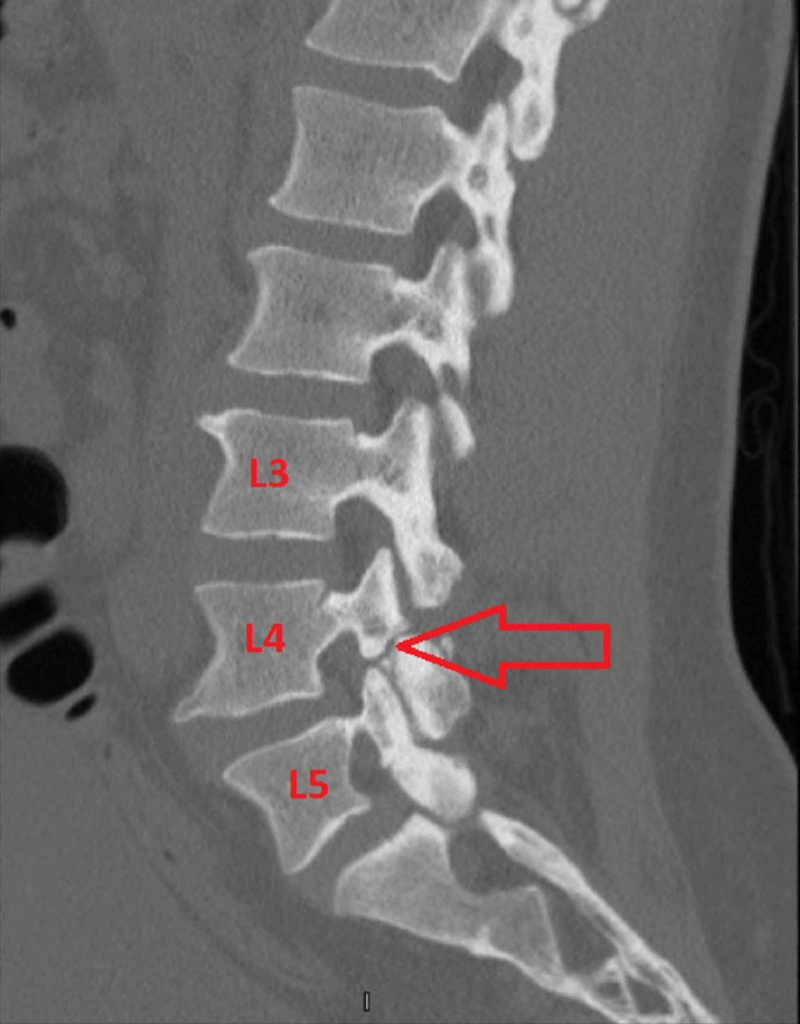

How is a pars fracture diagnosed on imaging?

It is difficult to diagnose in the early stages using regular x-rays, but there are two hallmark findings that can be seen on MRI and CT scan that can help with diagnosis: bone marrow edema of the adjoining pedicle on MRI and bone absorption at the caudal aspect on the sagittal reconstructed CT scan.